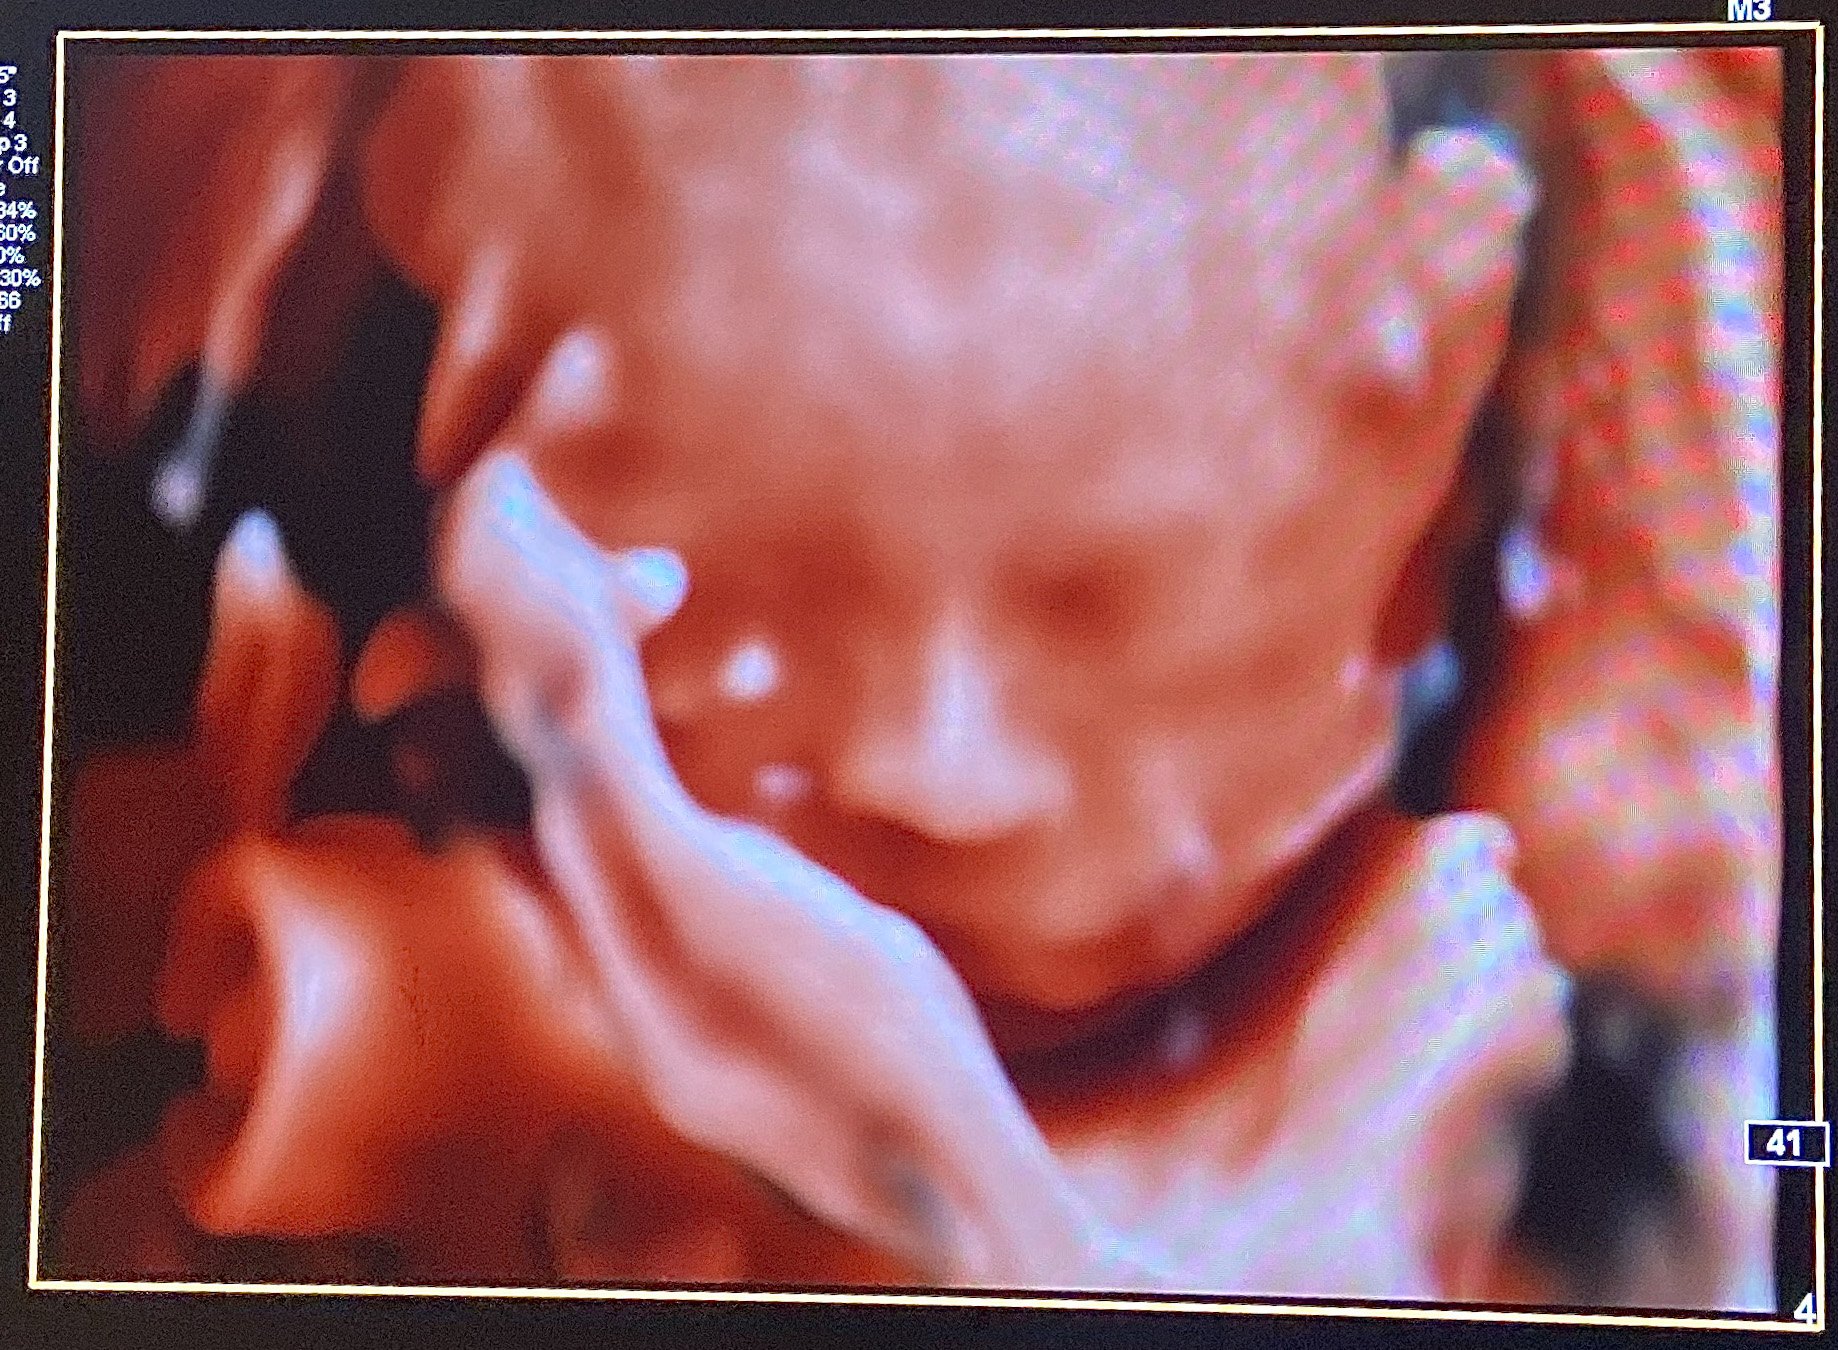

We had our follow up scan today to get the remaining pictures of baby girl's heart - all looks great, thank goodness! She's sucking her thumb here. She was still very active OR curled up in a ball and didn't want to move. Stubborn like her mama.

I go back at 32 weeks for a second growth scan which I wasn't aware was a thing but apparently it is! It's feeling really real now.